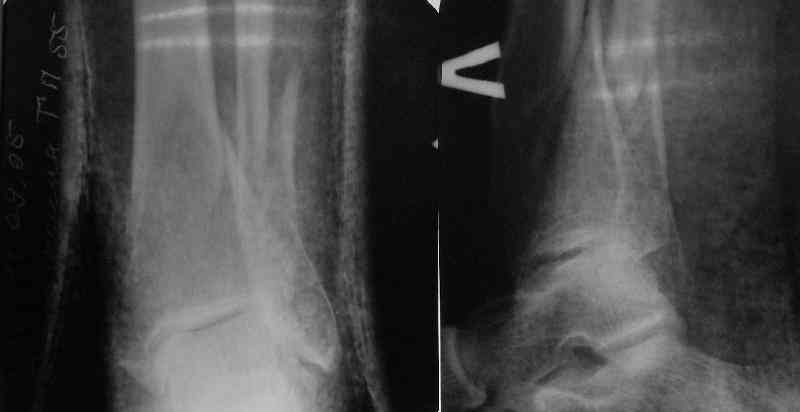

Направили к нам пациентку 35 лет с переломом дистального отдела костей голени.

У нас сделали снимок сзахватом обоих суставов - еще и проксимальный метафиз сломан. Чем бы у вас фиксировали такой перелом? Как его правильно закодировать по классификации АО?

Можно либо как два перелома - 41A+42B. А можно как один сегментарный 42С.

Today you have a complex fracture for classification.

Probably you need take a combination of two diferents fractures in the same bone.

41.A2.1 for a proximal fracture

42.B1.3 for a distal fracture

Is very difficult take an exactly AO/OTA group for a good classification Probably the locked IM nail is a good option.